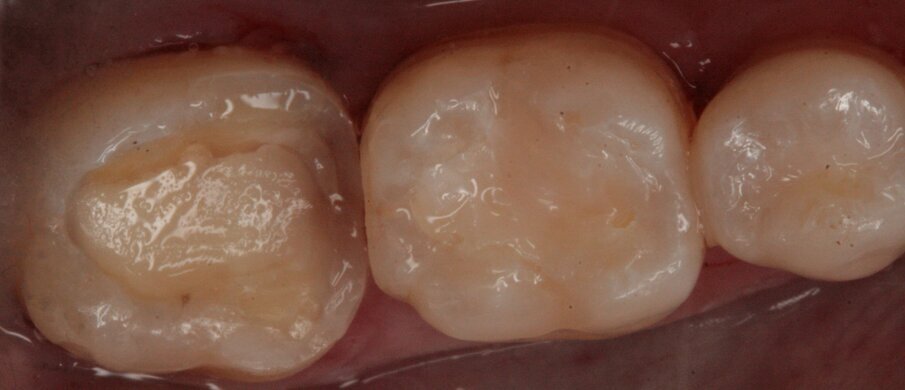

Gli elementi da trattare erano il 17, 16, 15 e 14 (Figg. 5, 6). Previo isolamento sotto diga (Fig. 7) si è proceduto alla cura dei suddetti elementi in un’unica seduta (Figg. 7-13). La lesione cariosa interessava anche la dentina sottostante perciò sono stati fatti piccoli incrementi di materiale al fine di consentire una stratificazione che garantisse un risultato estetico e funzionale.

Fig. 5_Visione occlusale di 16 e 17.

Fig. 6_Isolamento del campo operatorio.

Fig. 7_Preparazione delle cavità di 16 e 17.

Fig. 8_Restauri ultimati.